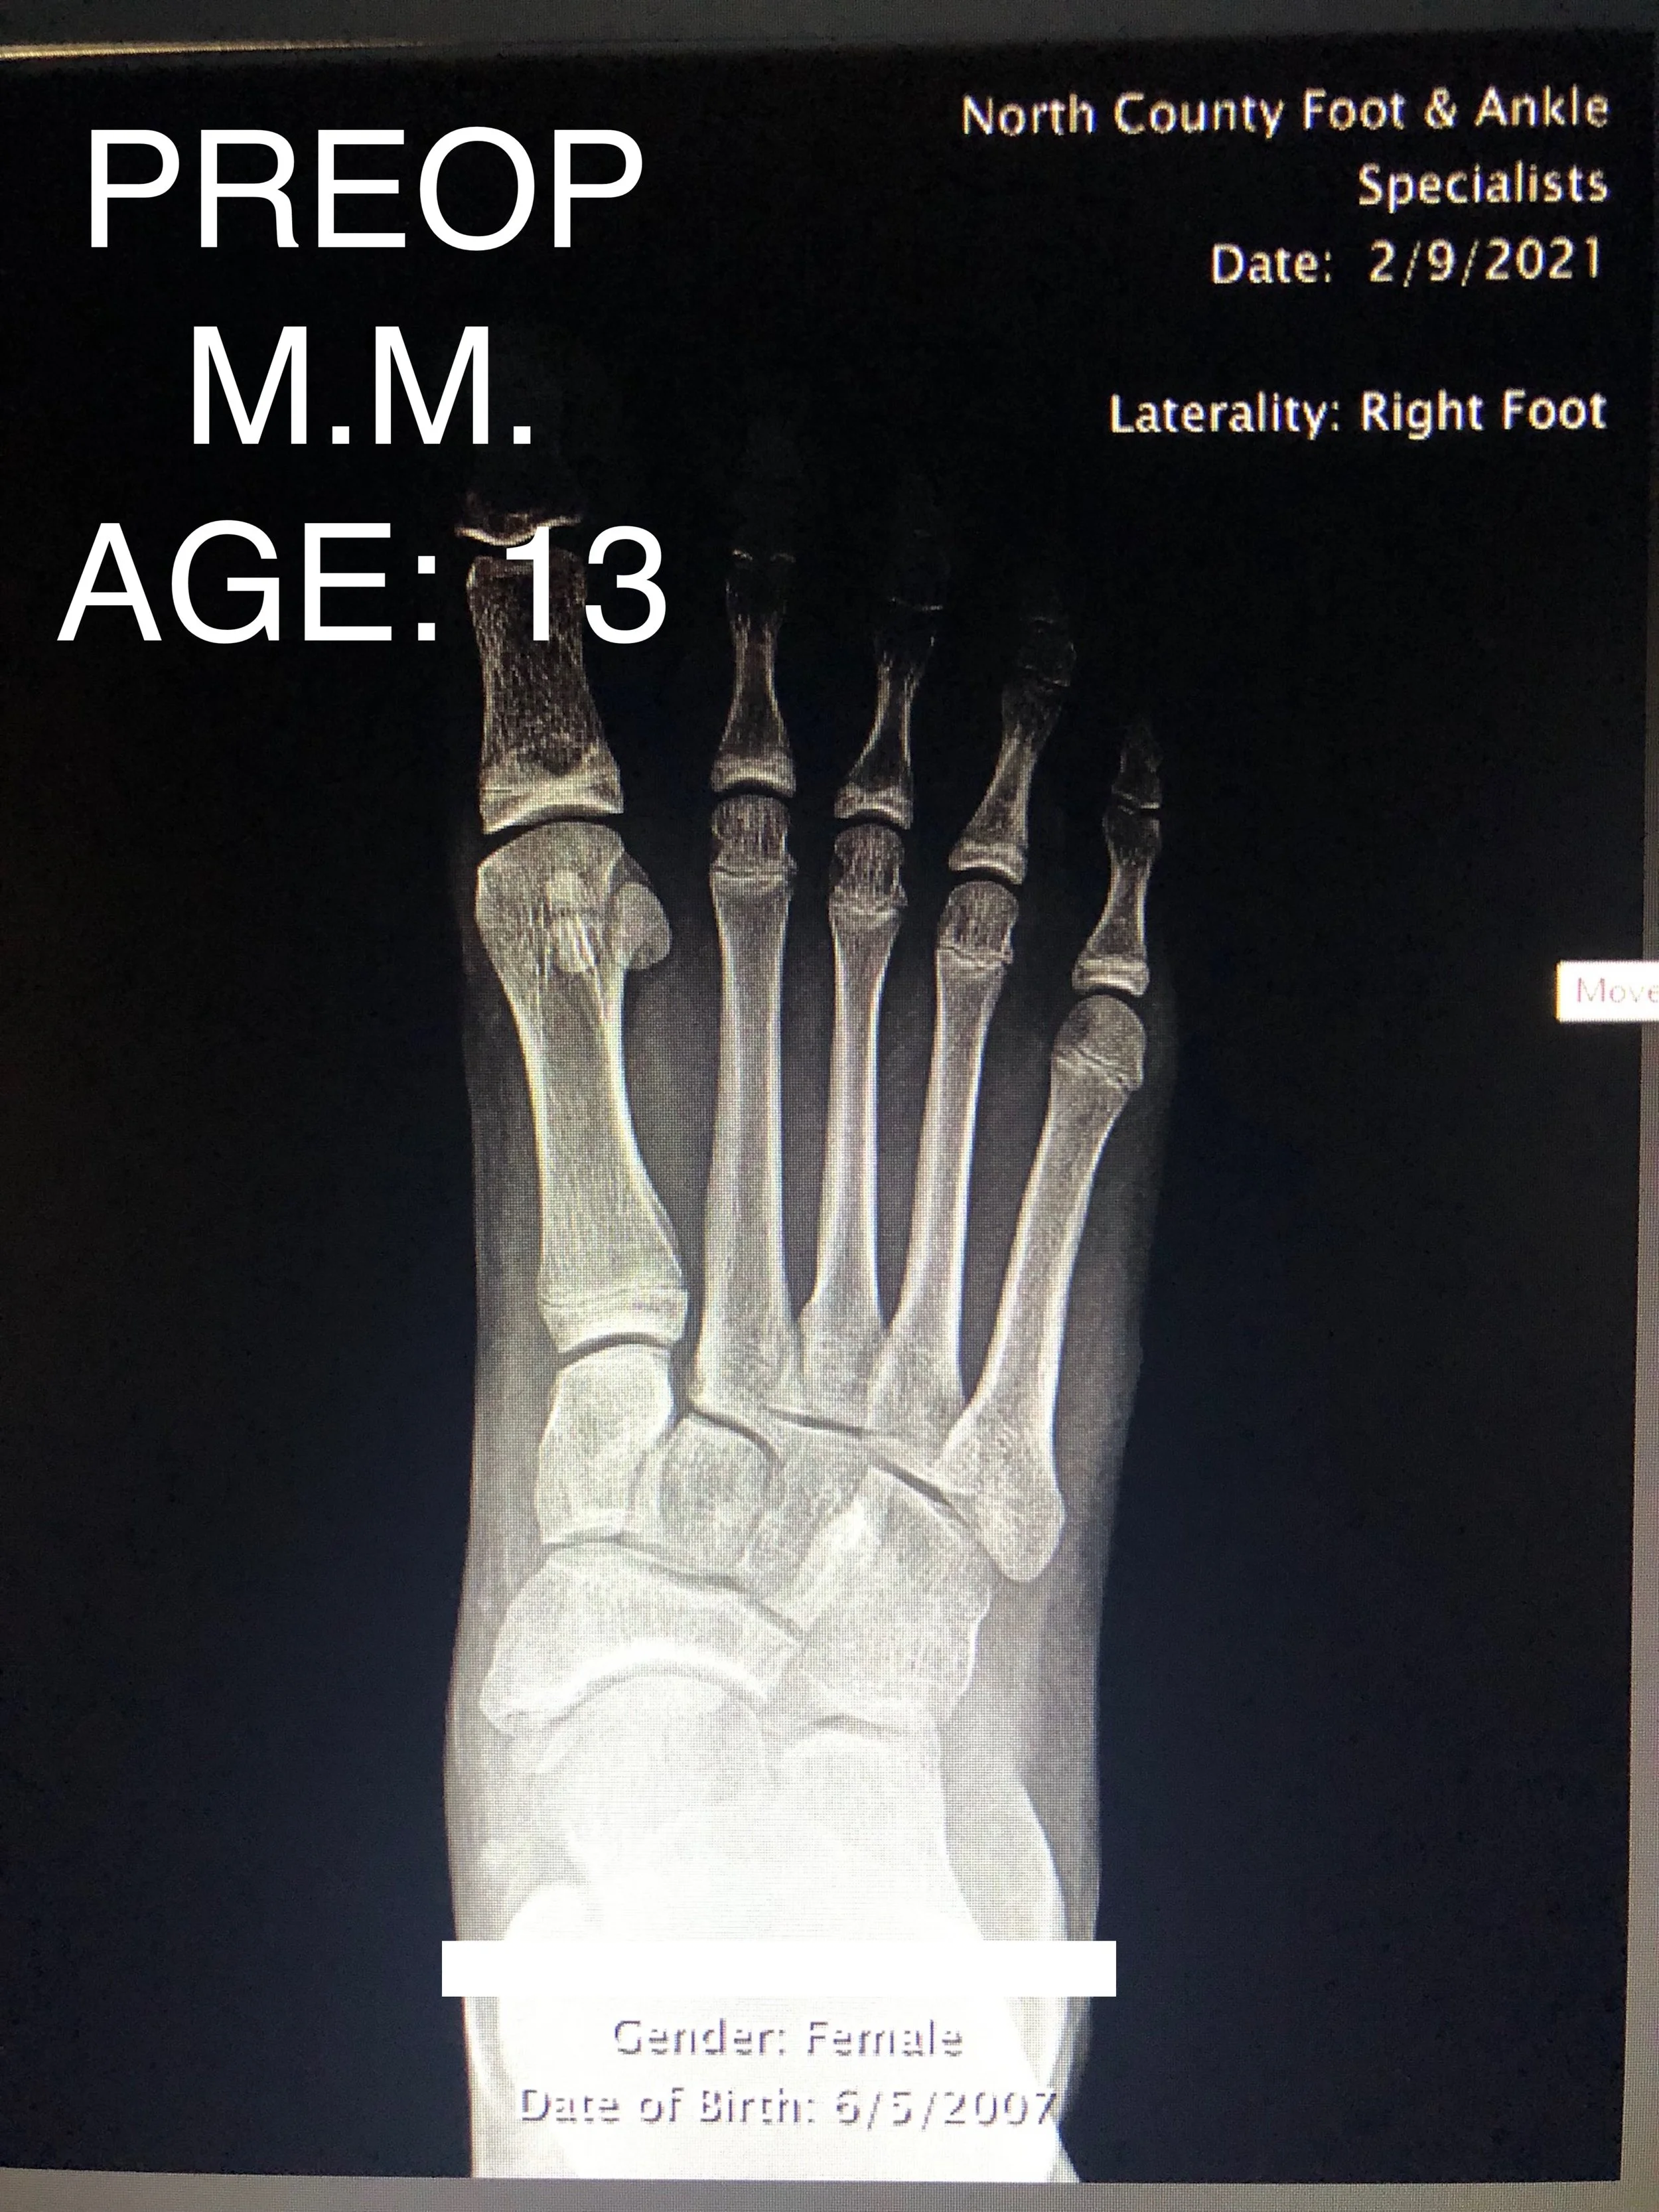

LAPIDUS